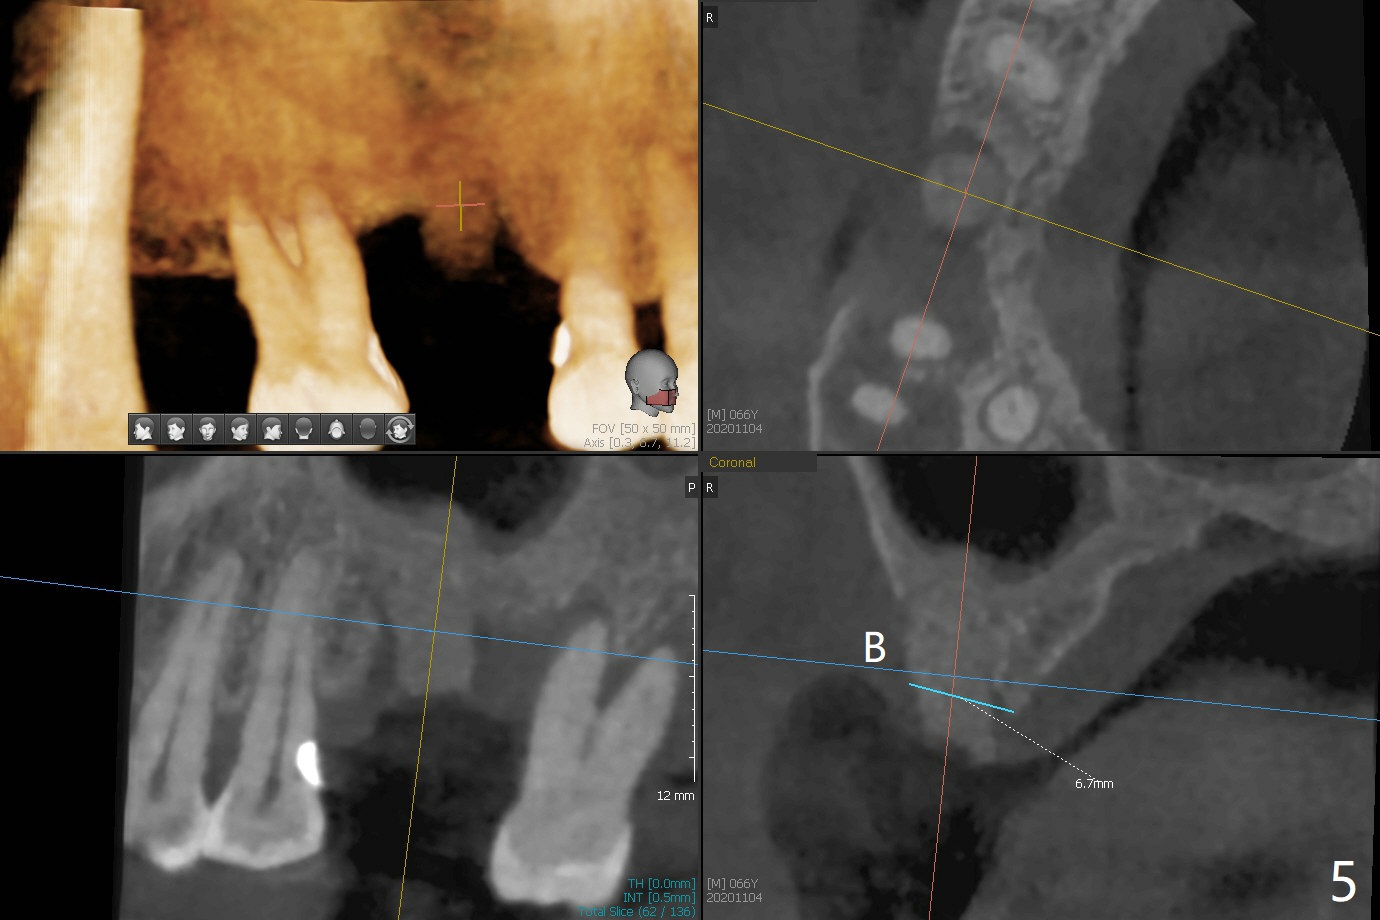

当3号牙短小植体植入后(图一(骨质密度高)),病人纳闷为什么不给他装临时牙冠,术后两个月又打电话要求提前修复,因为放置愈合基台,他无法使用局部托牙(单个牙),而14号牙即刻植牙即刻修复。他无法理解我们苦衷,有什么补救方法?

使用来自钻头的自体骨做提升,植体植入后,颊侧骨板薄,刚好骨下。使用5.5毫米profile drill后,放置愈合基台,术后三个月脱落,他再次要求修复,甚至提出退款,不愿意回诊所,因为他有糖尿病,新冠病毒高危人群。 放置小号愈合基台(图二)。他原来托牙是Valplast,没有occlusal rests,不能经过修改临时使用,可能将直接放置修复基台做临时牙冠。放置修复基台后(图三(术后三个月)),制作临时牙冠时,发现前者有些松动,后者就没有粘固。当基台完全就位,它最冠方与植体没有间隙(箭头),根方有间隙(空心箭头)。其实愈合基台也是一样(图一,二)。后来植体松动(术后4个月),拔除,植骨(图四),颊侧骨板缺失(图五:B)。植骨后5个月2号牙疼痛需要拔除种植(图七),与3号牙一起种植(图六),颊侧骨板修复,但是高度有所下降(箭头)。The narrow ridge with the intact buccal plate (Fig.8 >) can hold a 4x8.5 mm implant. The buccal plate is lost 4 months postop (Fig.9) and restores 5 months post graft (Fig.10). Return to Upper Molar Immediate Implant, No Deviation Coronal and Apical Gap in IBS implant Protect Graft Xin Wei, DDS, PhD, MS 1st edition 06/22/2020, last revision 05/02/2021